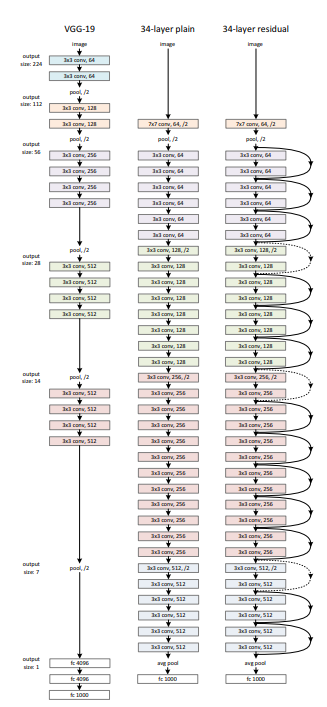

改进1是将原先unet的encoder修改为resnet,并使用其在imagenet上训练的预训练模型。

ResNet(Residual Network)是一种深度卷积神经网络(CNN)架构,主要特点是引入了残差连接(Residual Connection),即跨层跳跃连接,使得网络能够更有效地训练深层网络,并缓解了随着网络深度增加而出现的梯度消失和退化问题。虽然 ResNet 本身并不是专门为图像分割设计的,但其深度残差网络架构被广泛应用于各种视觉任务,包括图像分类、物体检测和图像分割。

ResNet 的核心设计思想是通过引入残差模块(Residual Block)来构建深度网络。每个残差模块由一组卷积层组成,但不同于传统的卷积层堆叠,残差模块通过跳跃连接(skip connection)将输入直接加到卷积输出上,从而形成“输入+卷积输出”的形式。这一设计让网络能够学习“残差”而不是直接学习目标映射,从而减轻了深层网络中信息传递的难度。

ResNet 架构由多个残差模块堆叠而成,其中每个残差模块可以是两层或三层卷积层。每层卷积之后通常会应用批归一化(Batch Normalization)和激活函数(如 ReLU)。在网络的深层,残差模块通常采用更大步幅的卷积来实现下采样(如步幅为 2 的卷积),使得特征图的分辨率逐步降低,同时通过残差连接保留了足够的特征信息。

ResNet 的设计可以有效地增加网络的深度,同时避免了深层网络中常见的退化问题。深度网络能够通过学习残差来“跳过”一些无关的特征,从而更容易训练。对于非常深的网络,ResNet 的残差连接有助于信息流的有效传递,保证了梯度在反向传播过程中的稳定性。

在图像分割任务中,ResNet 通常作为编码器部分的骨干网络(Backbone),负责提取图像的高层次特征。其输出特征图会被传递给解码器部分进行上采样和重建,恢复图像的空间分辨率,最终生成分割结果。在这种应用中,ResNet 通过其深层的特征提取能力,能够捕捉到图像中的复杂语义信息,适应各种分割任务,包括目标检测、医学图像分割等。

总体来说,ResNet 的结构设计使得其在深度学习领域特别适合于处理复杂和大规模的图像分割任务。通过残差连接的引入,网络能够在较深层次上保持有效的学习能力,并在分割任务中提供更加精确和细致的结果。